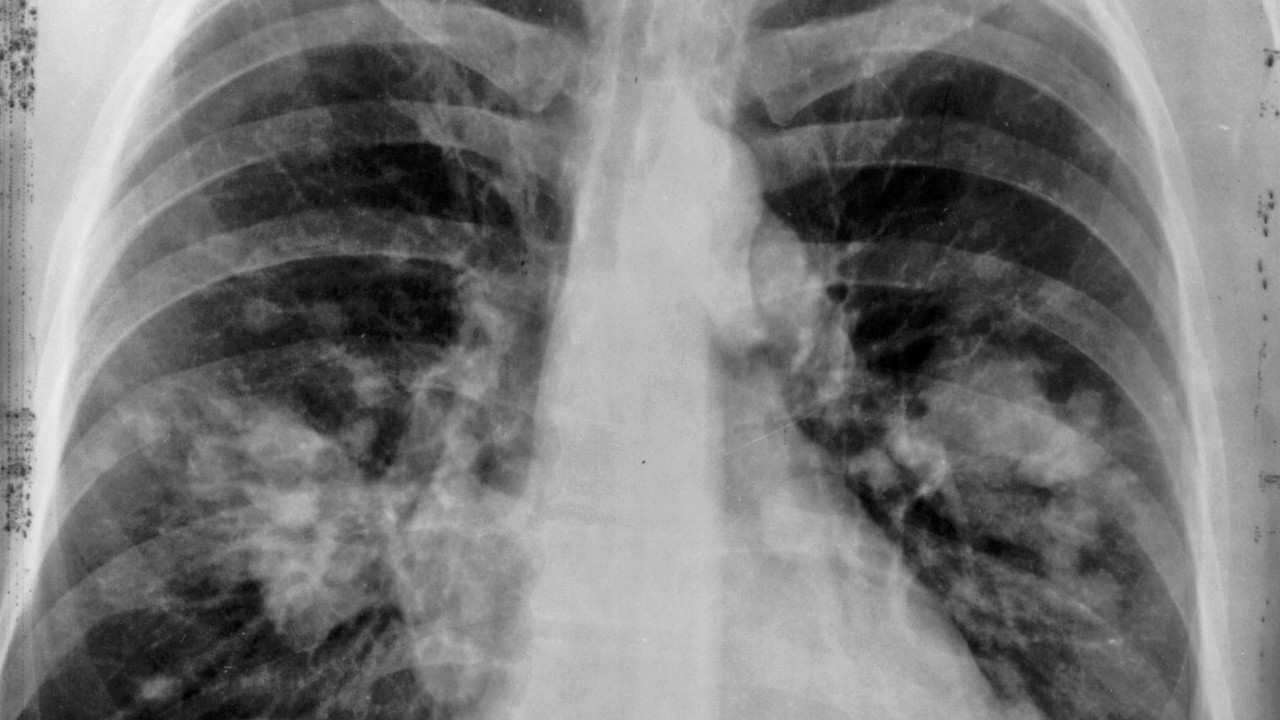

İnsanların akciğerlerine ilişkin yaşadığı sorunlar kişiden kişiye göre değişiyor. Yani kalıtsal bazı özellikler ve yaşam tarzı insanların akciğer sorunları yaşayıp yaşamayacağının önemli göstergelerinden. Sigara içmenin yanısıra akciğer sorunlarına neden olabilecek çok sayıda neden bulunuyor. Hatta insanların çoğunluğu, sorun yaşayana kadar akciğerlerinin olumsuz etkilenebileceğinin farkına varmıyor.

Sigara kullanılmasa da, havada akciğerleri olumsuz etkileyebilecek çok sayıda bileşen olduğu unutulmamalı. Toksinler, kimyasallar, gazlar ve toz parçacıkları solunan hava ile akciğerlerin içine girerek, ciğerlerimizde farkında olmadan hasara neden oluyor. O nedenle akciğerleri korumak büyük önem taşıyor.